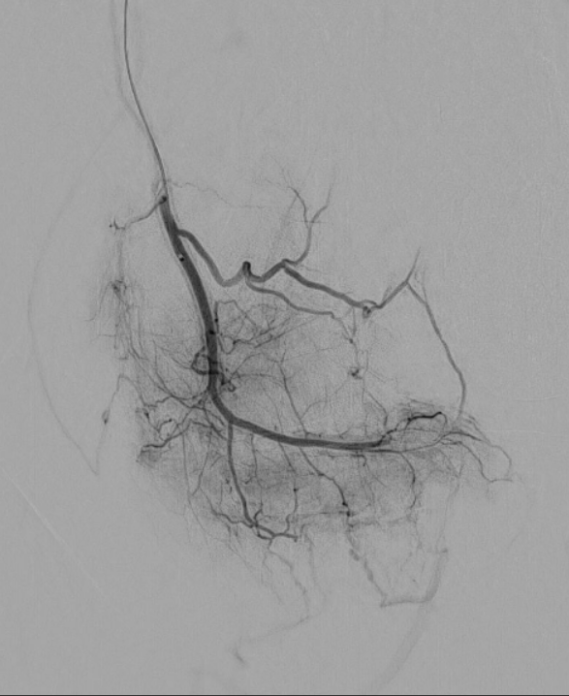

Letztlich sind alle diese längerfristig bestehenden Schmerzen durch eine chronische Entzündung bedingt. Dies ist keine bakterielle Entzündung, sondern eine "normale" Reaktion des Körpers. Es kommt zum Einsprossen von neuen, kleinen Blutgefäßen und neuen Nervenbahnen, welche die Schmerzen weiterleiten können.

Diese neuen, kleinen Blutgefäße sind der Angriffspunkt dieser innovativen Schmerztherapie. Durch dieses minimalinvasive Therapieverfahren erfahren Sie eine umgehende und lang anhaltende Schmerzlinderung.

Die Schmerzbehandlung durch transarterielle Mikroembolisation (TAME) ist eine innovative medizinische Behandlungsmethode, welche sich in den letzten Jahren stark verbreitet hat. TAME hat sich als effektive Option in der Schmerztherapie etabliert, da sie nicht nur die Lebensqualität der Patienten verbessert, sondern auch in vielen Fällen die Notwendigkeit von Schmerzmitteln verringert. Informieren Sie sich selbst - für Kritik, Anmerkungen oder Fragen stehe ich gerne zur Verfügung!